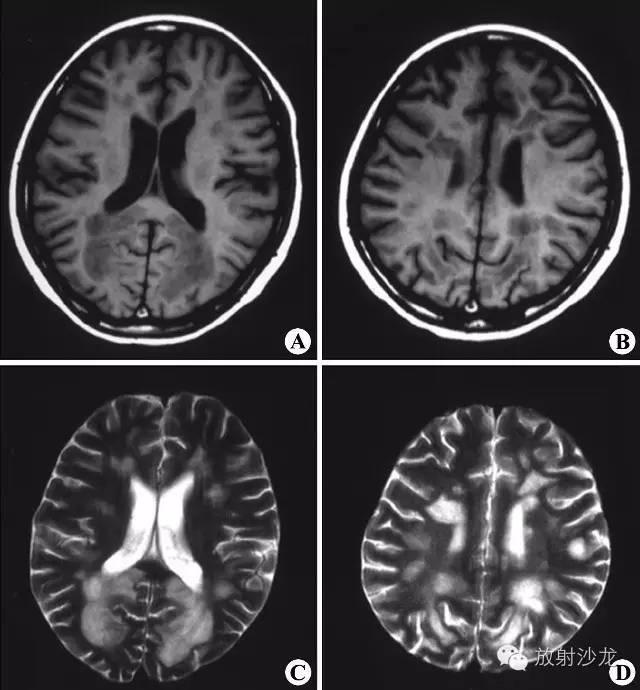

1.2影像学:MRIT1加权像见多发斑点状低信号病灶,通常与侧脑室壁垂直排列,与脑室周围白质内小血管的走行方向一致。陈旧性斑块呈等信号。由于多发硬化是少突神经胶质-血管髓磷脂复合疾病,因此有5%者,皮质和基底节亦受累,半卵圆中心的病灶可有占位效应。脊髓病灶呈长 条形,与脊髓长轴走行一致,一般脊髓不增粗。T2加权像病灶呈高信号,边缘清晰。质子密度加权像有利于显示靠近脑室边缘、脑干及小脑MS病灶。Gd- DTPA增强扫描T1加权像急性脱髓鞘病灶强化,陈旧病灶无强化。 MRI可判断MS的分期:MRI显示病灶大小不变、病灶缩小或数目减少,则提示为缓解期;若病灶增大或数目增多,则提示病情加重。MRI还可用来随访治疗效果。

MRI平扫示双侧侧脑室周围及深部脑白质多发斑片状异常信号区,T1WI(A、B)呈低信号,T2WI(C、D)呈高信号,未见占位效应